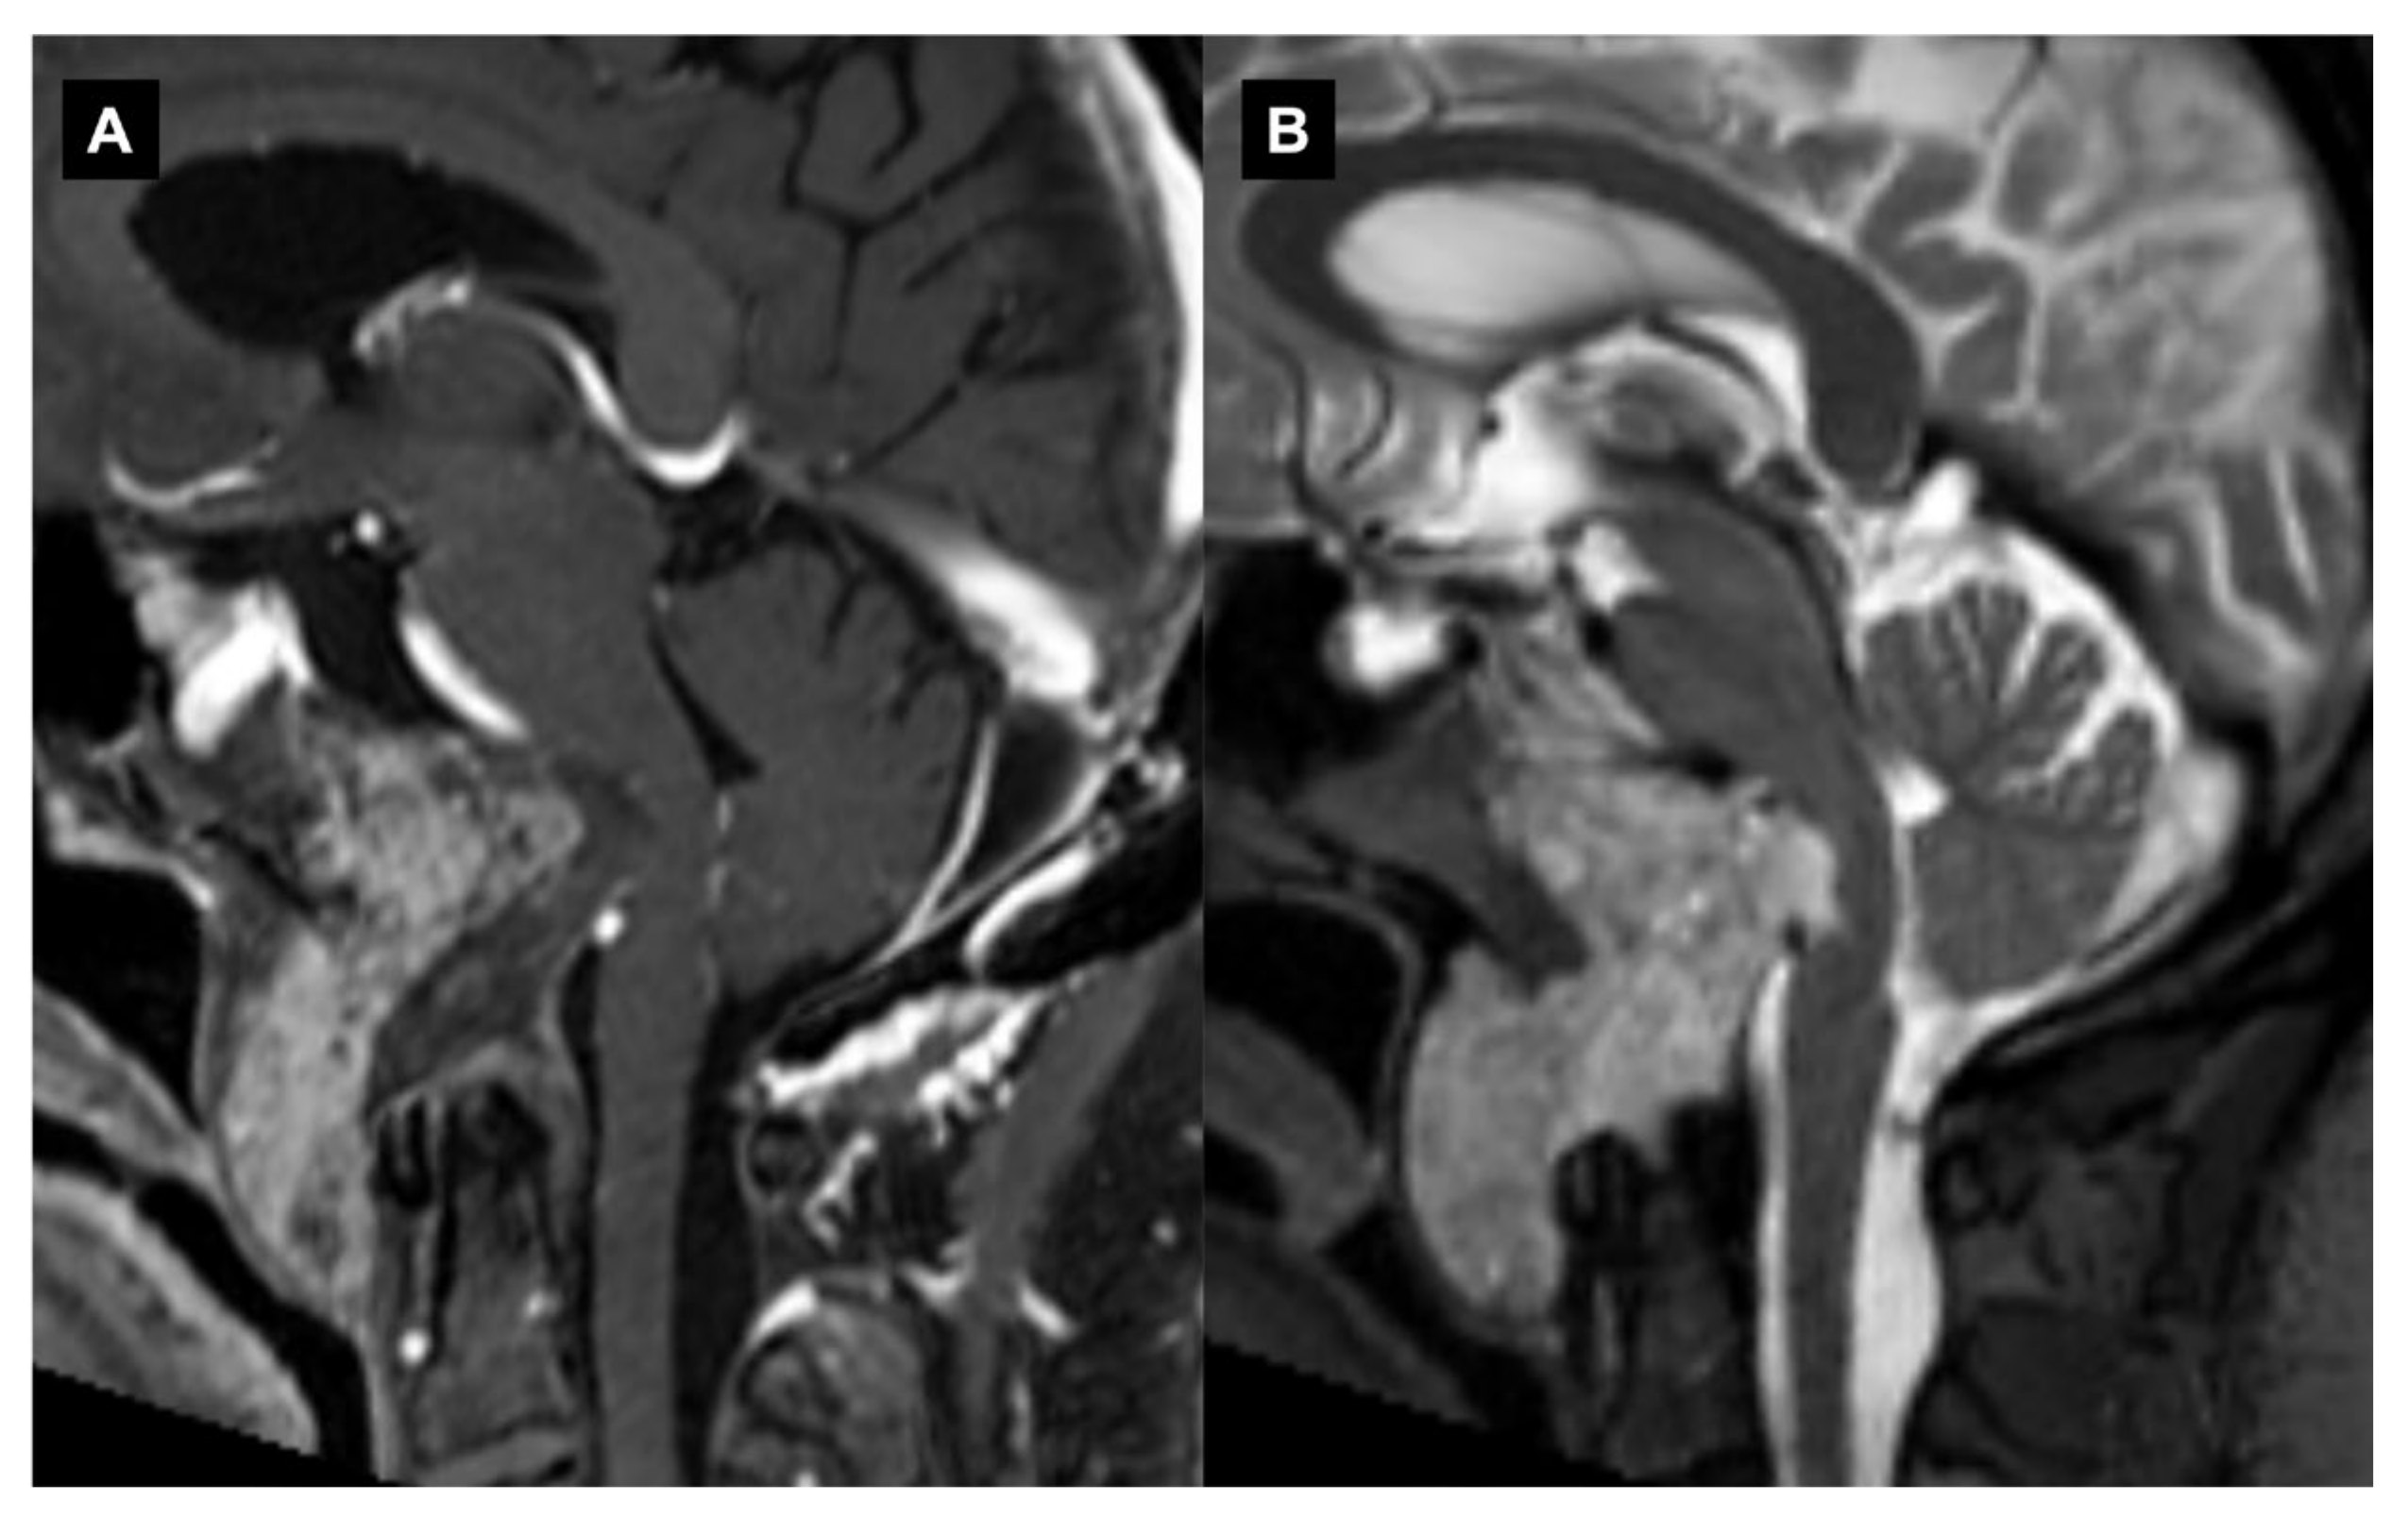

Figure 1.

Craniovertebral junction chordoma. Sagittal (A) T1-weighted image after contrast and (B) T2-weighted image depicting a large chordoma invading the rhinopharynx and extending into the premedullary cistern.

On CT, chordomas appear as well-defined expansile soft tissue masses that arise from the clivus with associated destructive lytic lesions and occasionally marginal sclerosis [43]. They appear as hypoattenuating heterogeneous lesions with areas of necrosis, hemorrhage and calcifications. Chordomas are iso/ipo-intense on T1-weighted MRI, with small hyperintense foci relative to intratumoral calcifications, hemorrhages or mucus pools. After contrast material injections, a honeycomb pattern of enhancement with intratumoral areas with a low signal intensity is typical. T2-weighed MRIs reveal a bright hyperintensity with heterogeneous hypointensities [38,44,45]. The “thumb sign” is a radiological finding that can be visible when chordomas project posteriorly at the midline and indent the pons [46].